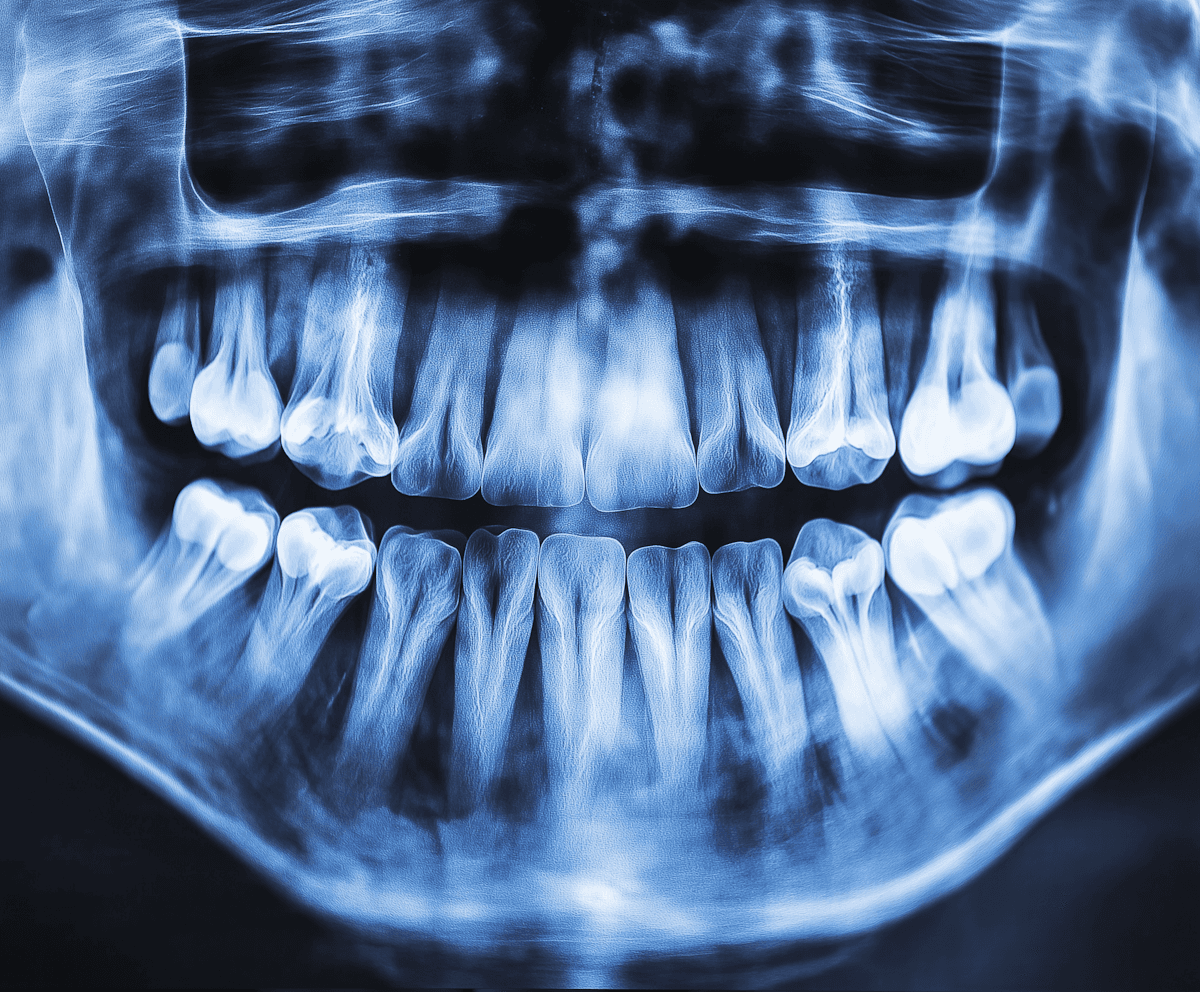

A 38-year-old patient, came to us with multiple dental issues including worn enamel, tooth discoloration, and mild misalignment. She expressed low confidence in her smile and often avoided social interactions. Her last dental visit was over three years ago, and she admitted to inconsistent flossing habits despite daily brushing. Emma reported a high coffee intake, occasional teeth grinding during stressful work periods, and a family history of periodontal disease.

The patient faced several dental concerns that significantly impacted both their oral health and self-confidence. Years of neglect due to dental anxiety had led to severe tooth decay, gum inflammation, and bite misalignment.

This case required a careful balance of aesthetics and function. The discoloration was deep enough that standard whitening alone would not provide the desired results. Additionally, the uneven spacing and chips meant we needed to address both shape and alignment without compromising her bite. Another challenge was her mild bruxism (teeth grinding), which could affect the longevity of cosmetic restorations if not managed properly.